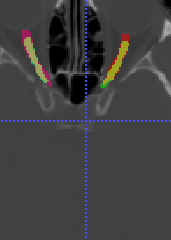

In Chapter 6, we propose an end-to-end, atlas-free 3D convolutional deep learning framework for fast and fully automated whole-volume HaN anatomy segmentation [115]. Our deep learning model, called AnatomyNet, segments OARs from head and neck CT images in an end-to-end fashion, receiving whole-volume HaN CT images as input and generating masks of all OARs of interest in one shot. AnatomyNet is built upon the popular 3D U-net architecture, but extends it in three important ways: 1) a new encoding scheme to allow auto-segmentation on whole-volume CT images instead of local patches or subsets of slices, 2) incorporating 3D squeeze-and-excitation residual blocks in encoding layers for better feature representation, and 3) a new loss function combining Dice scores and focal loss to facilitate the training of the neural model. These features are designed to address two main challenges in deep-learning-based HaN segmentation: a) segmenting small anatomies (i.e., optic chiasm and optic nerves) occupying only a few slices, and b) training with inconsistent data annotations with missing ground truth for some anatomical structures. We collect 261 HaN CT images to train AnatomyNet, and use MICCAI Head and Neck Auto Segmentation Challenge 2015 as a benchmark dataset to evaluate the performance of AnatomyNet. The objective is to segment nine anatomies: brain stem, chiasm, mandible, optic nerve left, optic nerve right, parotid gland left, parotid gland right, submandibular gland left, and submandibular gland right. Compared to previous state-of-the-art results from the MICCAI 2015 competition, AnatomyNet increases Dice similarity coefficient by 3.3% on average. AnatomyNet takes about 0.12 seconds to fully segment a head and neck CT image of dimension , significantly faster than previous methods. In addition, the model is able to process whole-volume CT images and delineate all OARs in one pass, requiring little pre- or post-processing. We demonstrate that our proposed model can improve segmentation accuracy and simplify the auto-segmentation pipeline. These contributions are released as an open-source software package called AnatomyNet, which is publicly available555https://github.com/wentaozhu/AnatomyNet-for-anatomical-segmentation. Portions of this chapter were published as part of [115].